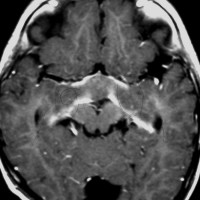

幼児の視路の毛様粘液性星細胞腫です。T2強調画像(左側)で白く高信号に写るのが特徴です。ガドリニウム増強ではまだらになっていますが,均一に真っ白に高信号になることも多いです。乳幼児のものは,ドロドロに柔らかい腫瘍です。

乳幼児時期には,病理組織像が毛様粘液性星細胞腫で,MRI T2で均一な高信号になりガドリニウムで強く増強されます。腫瘍の増大速度は速く,稀には髄液播種することもありそれが腫瘍死の原因となることもあります。奏効率の高い化学療法を早く開始する必要があります。